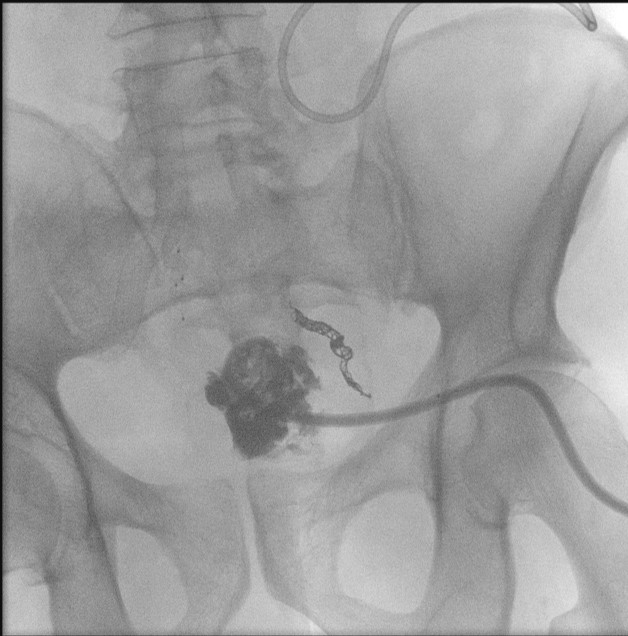

- When reviewing the preliminary scout film, you should see multiple surgical chain sutures in the pelvis

(key image 31)

(key image 32).

- After the enema tip has been placed but before contrast material has been administered, obtain a fluoroscopic spot film of the rectum with the patient in the left lateral position

(key image 33).

- As you instill contrast material into the J pouch, obtain images of the pouch and ileoanal anastomosis fully distended with contrast material in each of the following four (4) positions:

- left lateral

(key image 34)

- left posterior oblique

(key image 35)

- supine (AP)

(key image 36)

- right posterior oblique

(key image 37).